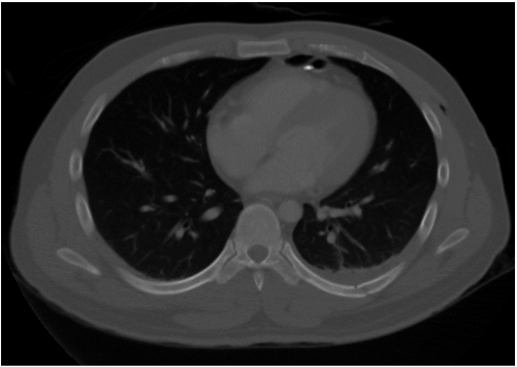

34.胸部電腦斷層攝影呈現如下圖,下列那一項最正確? (A)mediastinal window (B)lung window (C)bone window (D)pleural window